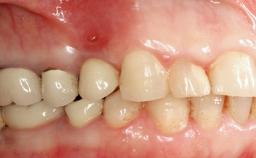

A 35-year old female patient was referred to the Department of Oral Surgery and Stomatology at the University of Bern, Switzerland, for examination of an implant site that had exhibited clinical signs of slightly delayed wound healing. In addition, the referring clinician found no evidence for a facial bone wall when she raised a flap to gain access to the implant for abutment connection. Four months earlier, she had inserted a bone-level implant in a single-tooth gap, where the lateral incisor had been extracted due to a chronic periapical lesion on the mesial aspect of the root. Implant placement was combined with simultaneous bone augmentation using deproteinized bovine bone mineral (DBBM, Bio-Oss®; Geistlich, Wolhusen, Switzerland) and a collagen membrane (Bio- Gide®; Geistlich), followed by primary wound closure. The patient also provided the postsurgical radiograph that displayed the implant with a 3.5-mm healing cap.